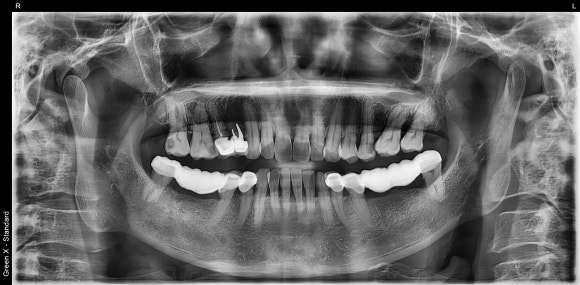

20241230

오른쪽 위 작은 어금니에 탈이 났습니다.

더 이상 치료를 할 수 없는 상황이라

부득이하게 발치를 권해드렸습니다.

20250415

수술 두 달 후,

임플란트가 뼈에 단단하게 고정된 것을

확인하고, 머리를 만들어 올립니다.